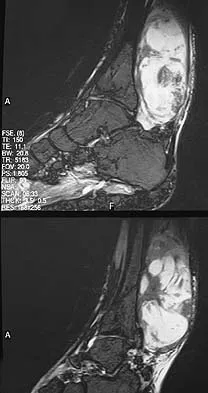

Question 646High Yield

Figures 13a and 13b show the MRI scans of a 70-year-old patient who has a posterior calf mass. Examination reveals that the mass extends to the midcalf level. A biopsy specimen reveals a high-grade soft-tissue sarcoma. Metastatic work-up shows no lesions. Management should consist of

Explanation

Soft-tissue sarcomas generally are treated with radiation therapy and wide surgical resection. In this patient, involvement of most of the posterior calf compartment and circumferential involvement of the posterior tibial and peroneal neurovascular bundle makes limb salvage impractical. Any attempt at wide surgical resection would leave a poorly functioning limb with questionable surgical margins. A high below-knee amputation would be the best option. Radiation therapy alone is contraindicated. Lindberg RD, Martin RG, Romsdahl MM, et al: Conservative surgery and post-operative radiotherapy in 300 adults with soft tissue sarcoma. Cancer 1981;47:2391-2397. Sim FT, Frassica FS, Frassica DA: Soft tissue tumors: Diagnosis, evaluation, and management. J Am Acad Orthop Surg 1994;2:202-211.